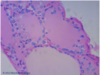

Identify: